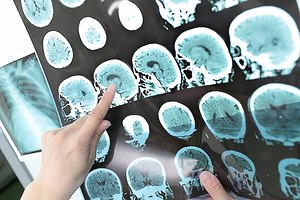

הטיפול בשבץ מוח: כל החידושים

הטיפול בשבץ מוחי השתפר מאוד: צנתור המוח השתכלל ונכנס...

מערכת zap doctors 07/01/2017